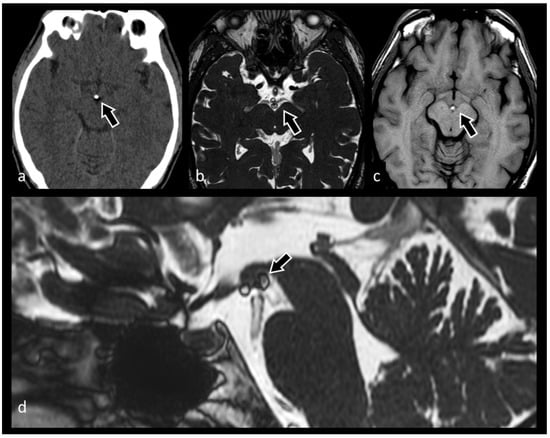

3.5. Hydrocephalus, Ventricular System and Subarachnoid Cisterns

3.7. Evaluation of Brain Tumors

3.9. Hypothalamic–Pituitary Disorders